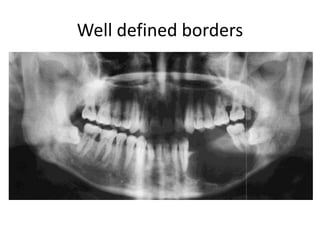

Malignant tumors

• Sarcoma

• Carcinoma.

• Metastasis.

Benign tumors

• Growth by direct extension

• Insidious onset

• Well defined borders

• Rl + RO

• Tooth displacement, or

root resorption

• Expansion or thinning of

cortical bone

Growth by infeltration and

distruction

Sudden onset

Ill defined borders

Punched out borders

Totally RL

Destruction of alveolar

bone, teeth floating or

displaced occlusally

Erosion and destruction

of cortical bone

Well defined borders